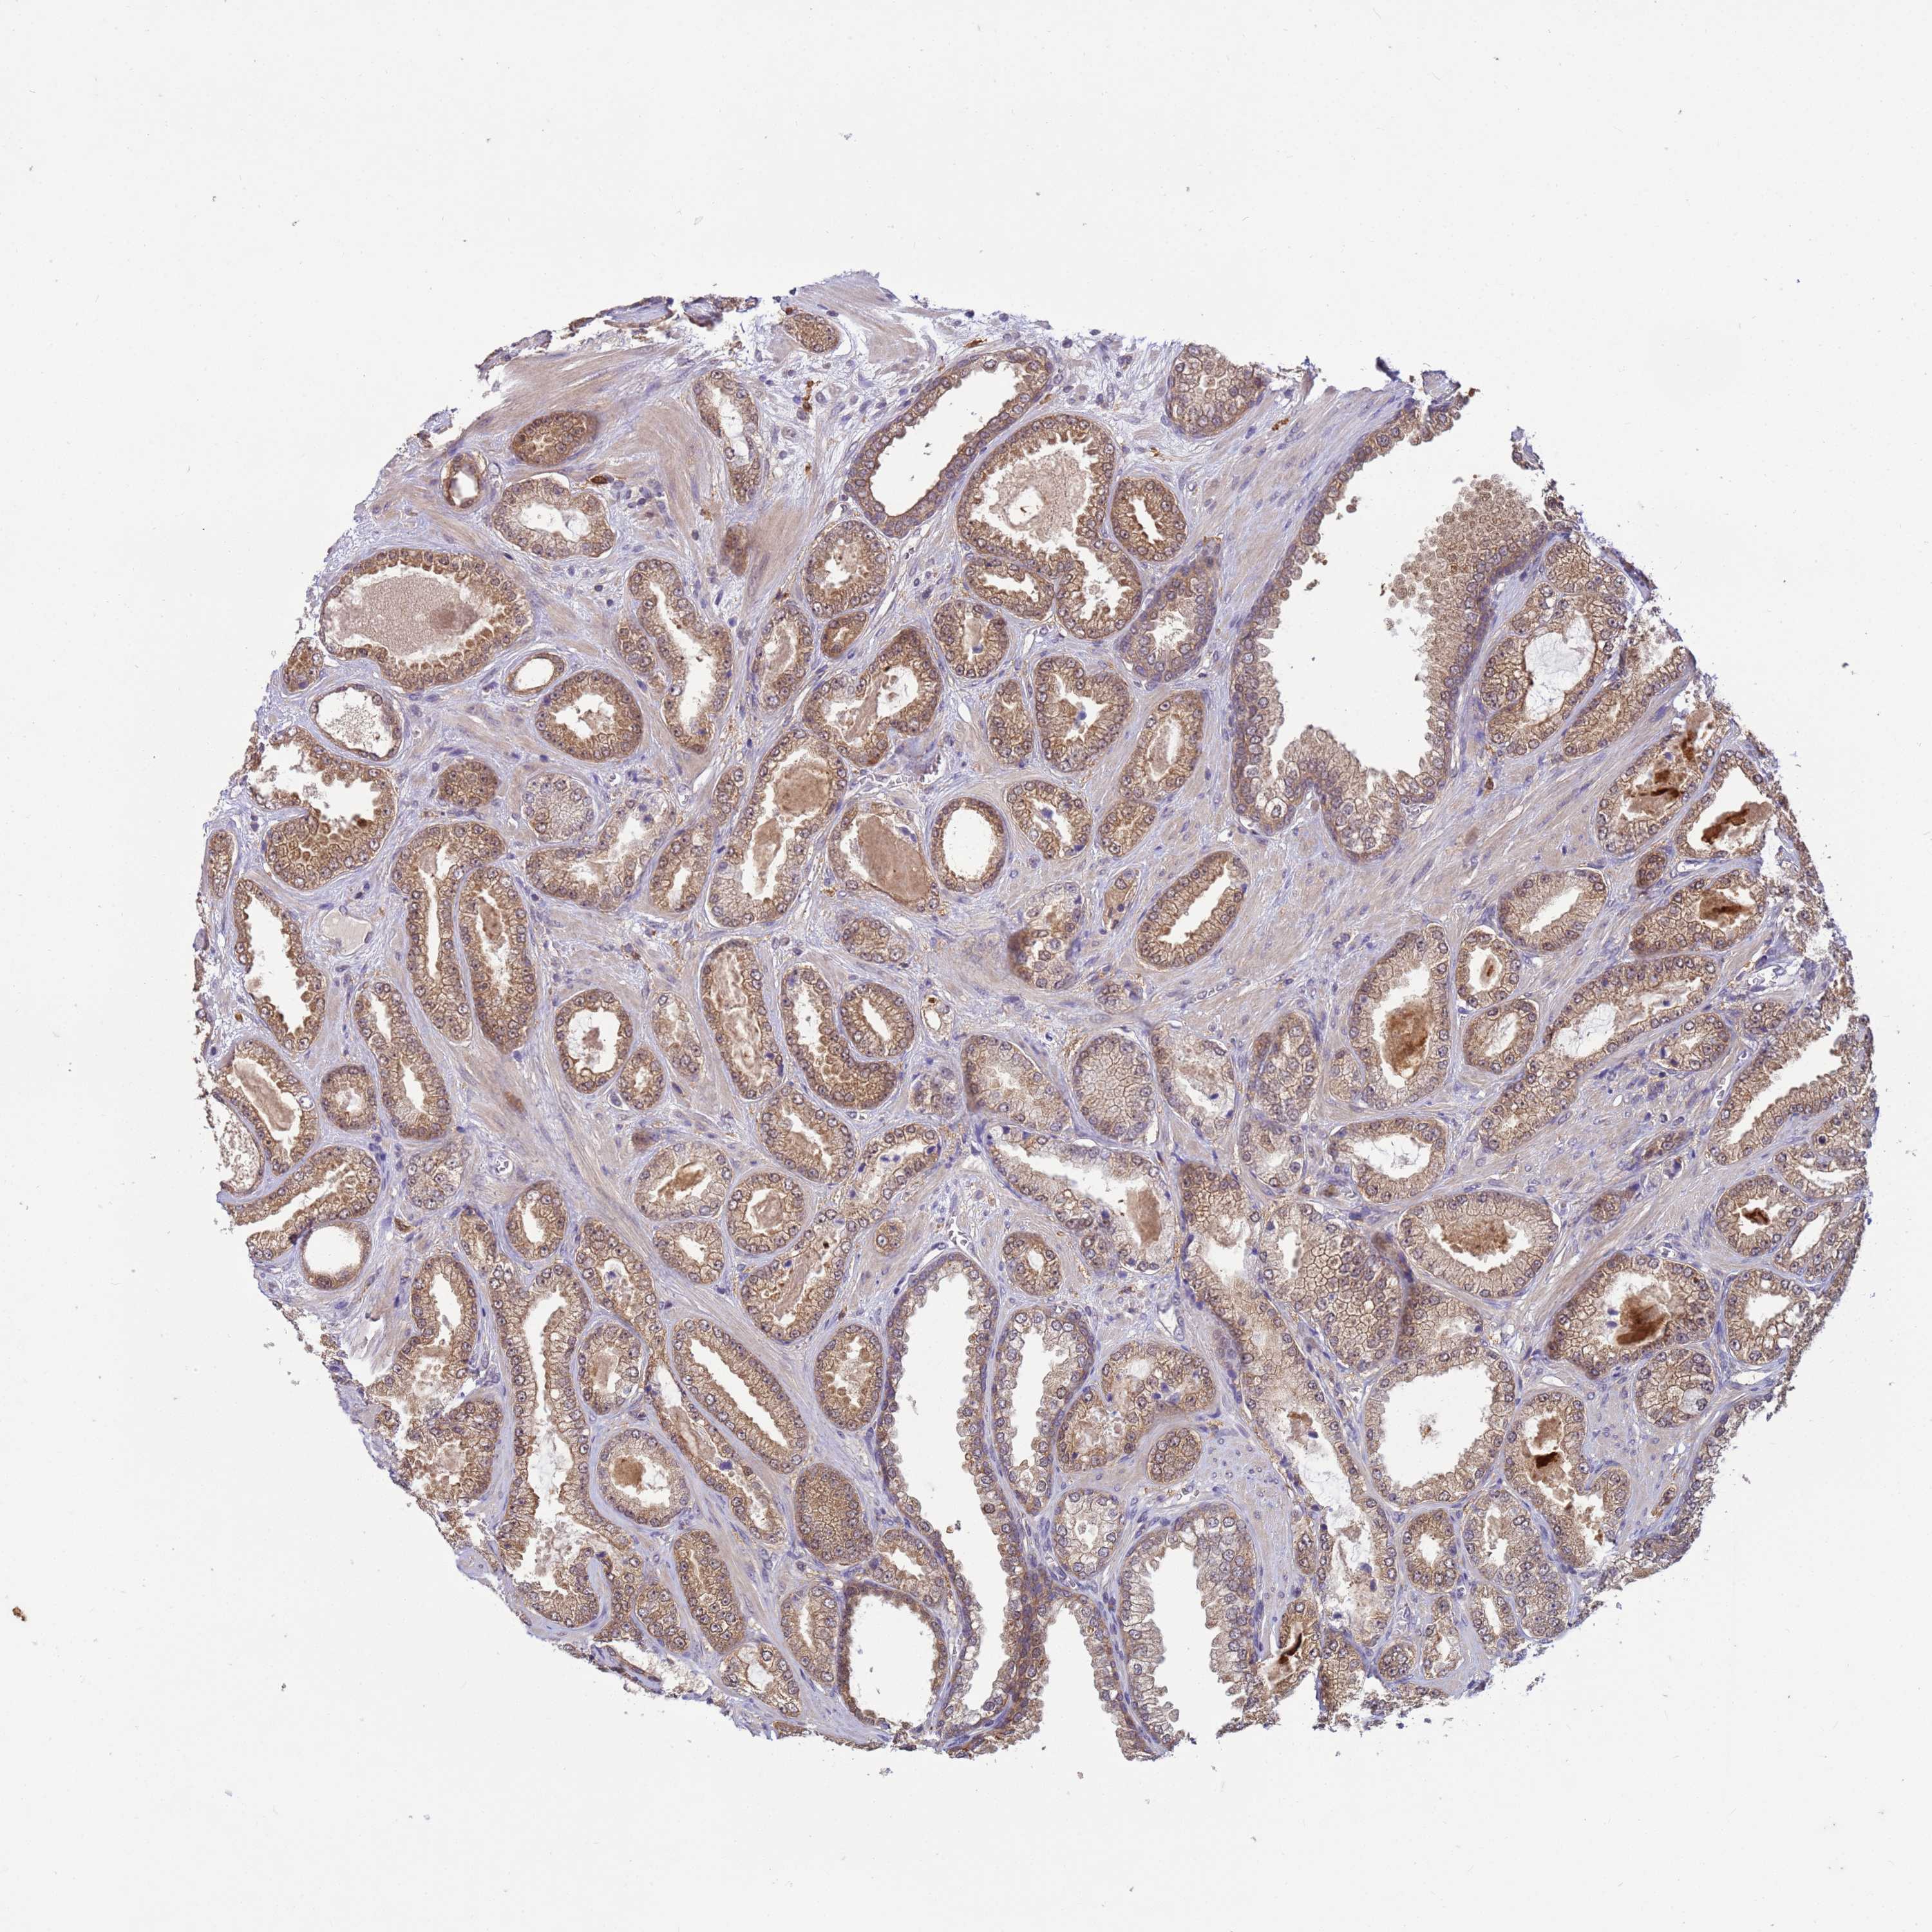

PROSTATE CANCER - Protein expressioni

A mouse-over function shows sample information and annotation data. Click on an image to view it in a full screen mode. Samples can be filtered based on level of antibody staining by selecting one or several of the following categories: high, medium, low and not detected. The assay and annotation is described here.

Note that samples used for immunohistochemistry by the Human Protein Atlas do not correspond to samples in the TCGA dataset.

Antibody stainingi

Antibody staining in the annotated cell types in the current human tissue is reported as not detected, low, medium, or high, based on conventional immunohistochemistry profiling in selected tissues. This score is based on the combination of the staining intensity and fraction of stained cells.

Each image is clickable and will lead to virtual microscopy that enables deeper exploration of all samples and also displays staining intensity scores, fraction scores and subcellular localization as well as patient and tissue information for each sample.

Antibody HPA021453

Antibody HPA045649

Staining

High

Medium

Low

Not detected

Intensity

Strong

Moderate

Weak

Negative

Quantity

>75%

75%-25%

<25%

None

Location

Nuclear

Cytoplasmic/membranous

Cytoplasmic/membranous,nuclear

Adenocarcinoma, NOS

Adenocarcinoma, High grade

Adenocarcinoma, Low grade